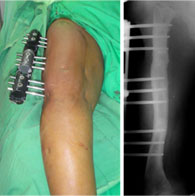

This patient had a congenital short femur with dysplasia of the hip on right side. She had undergone the lengthening of the femur earlier. She presented again with a progressive deformity as shown in the picture on the left side.

Now she had an apparent varus deformity with shortening of the right side.

When the full length x-ray was done it showed an oblique plane deformity which would require correction at two levels.

The appearance in the frontal plane once the varus angulations are corrected and the LRS (Limb Reconstruction System) assembly is completed.

The picture on the right is the x-ray appearance with the corrected bony axis. |